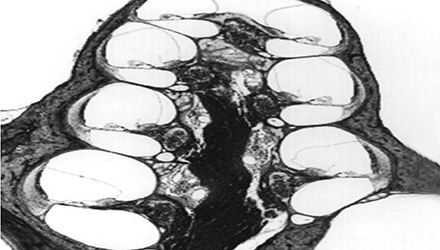

3、膜迷路破滅

膜迷路積水致膜迷路脹破,內(nèi)外淋巴液混合,刺激神經(jīng)感覺細(xì)胞導(dǎo)致眩暈、耳鳴、耳聾,裂口愈合則病變暫時(shí)恢復(fù)。下圖左為前庭膜膨大,右圖為前庭膜破裂,內(nèi)外淋巴交混。